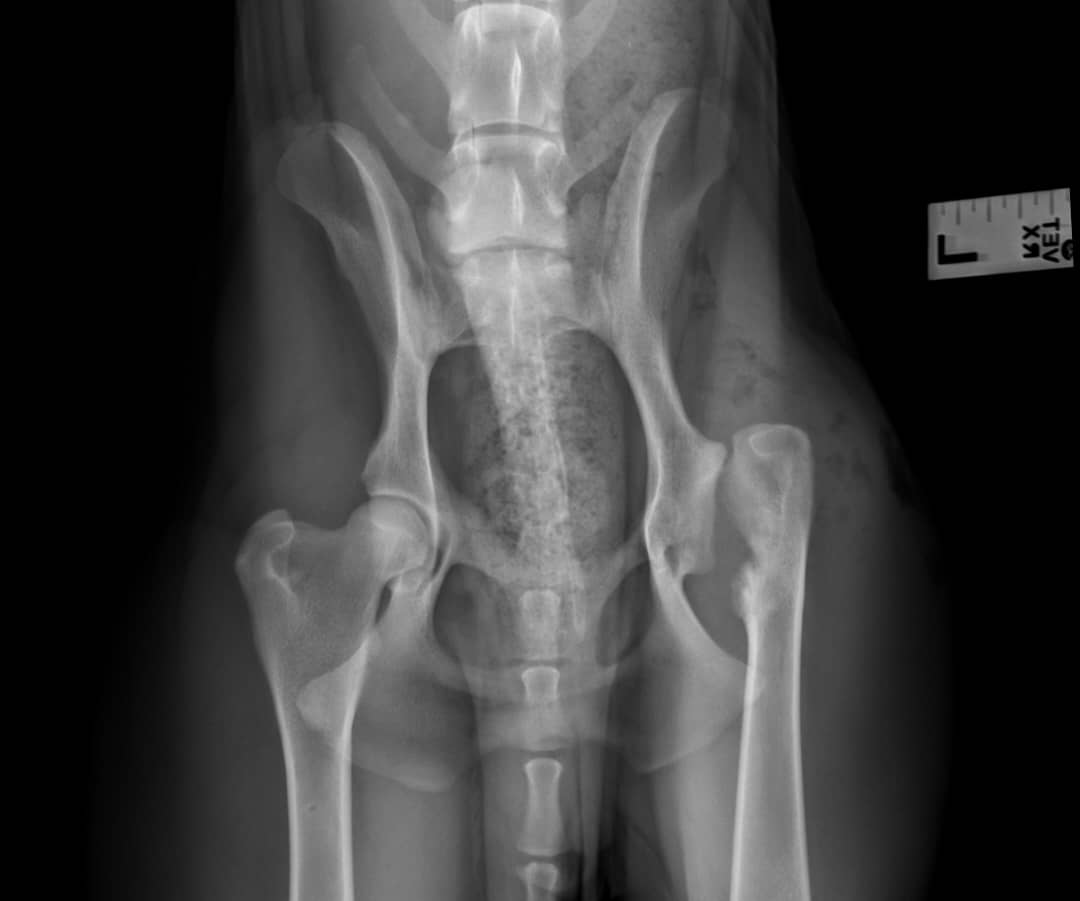

HÜFTDYSPLASIE und ellenbogenDYSPLASIE

Ursachen, Diagnose und moderne Behandlungsmöglichkeiten für schmerzhafte Gelenkerkrankungen bei Hund und Katze.